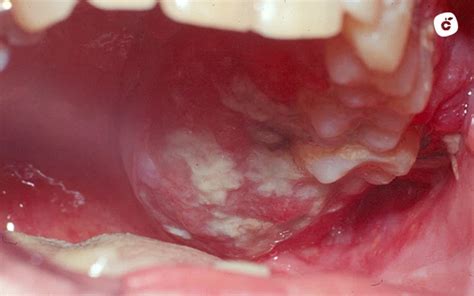

- Leucoplasia: Se produce cuando las encías se vuelven blancas. La leucoplasia puede aparecer en forma de manchas blancas indelebles o incluso cubrir partes enteras de la mucosa oral. Dependiendo de la forma, entre el 3 y el 38% de las leucoplasias se convierten en carcinoma de células escamosas. Se desarrollan cuando la mucosa oral se queratiniza en exceso.

En el caso del cáncer de encías, el tumor crece fuera de la encía en forma de úlcera y al principio parece una hinchazón, o bien crece hacia dentro, dejando un "cráter". También se denomina lesión ulcerosa. Si el dentista realiza un diagnóstico precipitado e incorrecto e inicia el tratamiento, puede tener consecuencias muy perjudiciales.